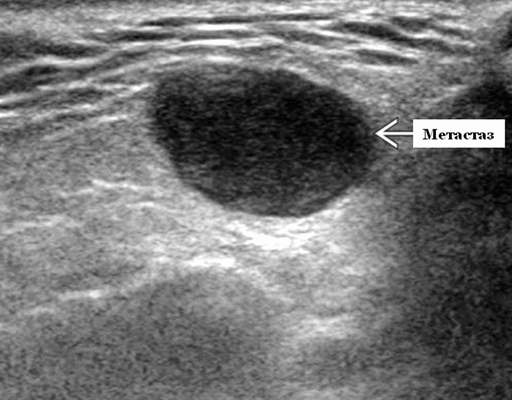

Данные ультразвукового исследования слюнных желез

- Одиночные или множественные гипоэхогенные образования при известном распределении внутрипаротидных лимфоузлов.

- На ультразвуковом сканировании образование четко или плохо определено (экстранодальное распространение)

- На УЗИ определяется аномальная внутренняя архитектура ± эхогенные ворота, эхогенность однородная или неоднородная с внутренними кистозными участками в некротических узлах

- Интранодулярный кровоток хаотичный / дезорганизованный или преимущественно периферический

Визуализация. Общие особенности. Само по себе ультразвуковое сканирование метастазов в околоушные лимфоузлы неспецифична. Одиночные или множественные околоушные образования. Хорошо выраженный или плохо выраженный лимфоузел (экстранодальное распространение), однородный или неоднородный с внутренним некрозом. На УЗИ с ЦДК внутриузловая васкуляризация или усиление кровотока. Патология связана с известным первичным раком, часто в прилегающей коже или региональной области головы и шеи. Околоушные и перипаротидные узлы: узловая станция 1-го порядка при плоскоклеточной карциноме кожи (ПКК) и меланоме латеральной части волосистой части головы, ушной раковины / наружного слухового прохода и передней части лица

Серошкальное УЗИ. Одиночные или множественные гипоэхогенные образования в известном распределении внутрипаротидных лимфоузлов. Хорошо выраженный или слабо окаймленный (экстранодальное распространение). Экстранодальное распространение. Обратите внимание на местную инвазию интрапаротидной наружной сонной артерии (ВСА), ретромандибулярной вены или экстрапаротидных мягких тканей. Аномальная внутренняя архитектура ± эхогенные ворота. Однородный или неоднородный вид с внутренними кистозными участками в некротических узлах ± метастазы в шейные лимфатические узлы